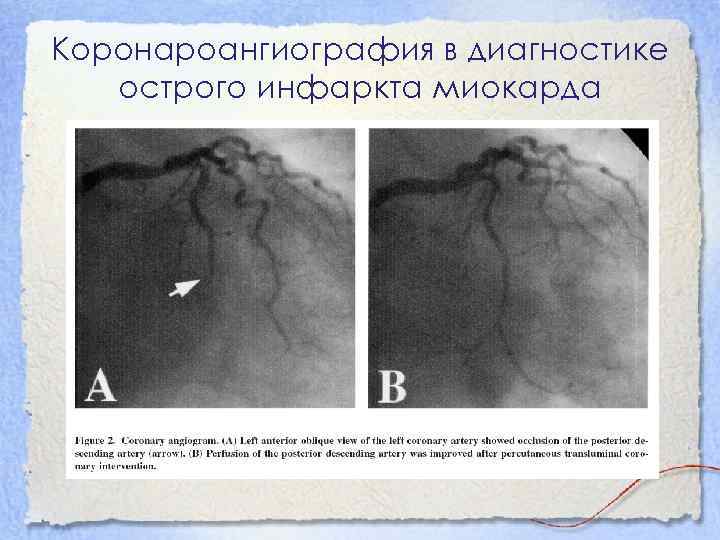

Хроническая окклюзия артерий: причины, симптомы и лечение